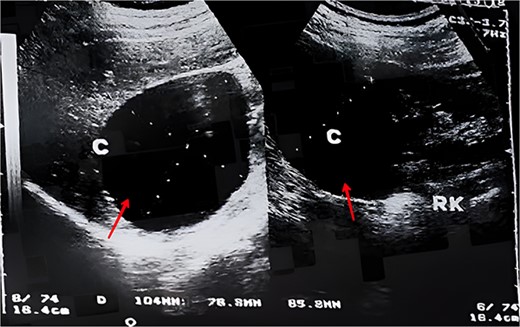

A 17-year-old female presented with mild pain in her right flank for the past 4 months. The pain was non-radiating and not associated with nausea or vomiting. The patient had the same complaint a year ago, which was disregarded because of the lack of access to a healthcare center. The pain did not relieve on medication and the patient was referred to our department. On physical examination, the abdomen was soft and non-tender without distention. There was no dysuria, hematuria, or fever. There was no history of weight loss, loss of appetite, or change in bowel movement. The patient had normal puberty, current menstrual cycle is regular and no hirsutism was observed. Patient’s past medical and surgical history was insignificant. Vital signs and blood tests were within normal. Renal/hepatic function panel was within normal range. Abdominal ultrasound showed a large cystic lesion measuring 9 × 9 × 12 cm on the right kidney (Fig. 1). Subsequent abdominal computerized tomography (CT) with contrast showed a large, well-defined, clear fluid-filled suprarenal cyst posterior to the liver, isolated from the liver, right kidney, and the right adrenal gland measuring 8 cm (Fig. 2A–B). Depending on the imaging results which were mistakenly found consistent with a mesenteric cyst, we opted for laparoscopic surgery since the cyst was symptomatic. A surgical exploration of the abdomen revealed an adrenal cyst. The cyst was excised along with the right adrenal gland. Histopathological examination of the resected cyst showed the cystic wall lined by a single layer of cuboidal or flattened epithelium with other sections of normal adrenal cortex tissue, confirming the diagnosis of an epithelial adrenal cyst (Fig. 3). The patient was discharged the next day, her recovery was uneventful and the pain resolved after the removal of the adrenal cyst and did not require further treatment.

An ultrasonography image showing a cystic mass (arrow) measuring 9 × 9 × 12 cm on the right kidney.